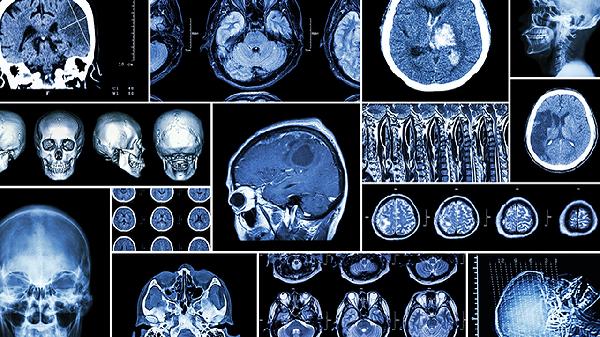

日常需监测记忆变化情况,发作时记录持续时间与伴随症状。控制心血管危险因素,避免过度疲劳和情绪激动。若失忆发作频繁或伴随肢体麻木、言语障碍等症状,应立即前往神经内科就诊。长期未缓解者需进行头颅核磁共振与脑电图检查,排除器质性病变后可通过正念冥想等非药物手段改善脑功能。